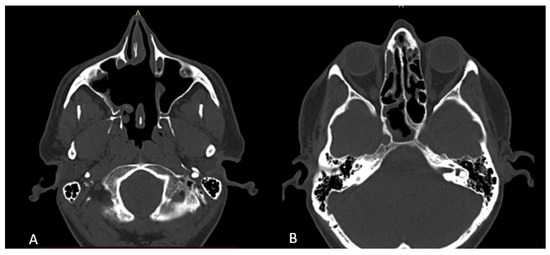

2. Case Presentation

3.2. Diagnosis and Radiological Features